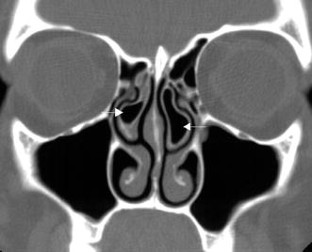

Radiological imaging of inflammatory lesions in the nasal cavity and paranasal sinuses

Paranasal sinus development and pneumatisation variants are described, and rhinosinusitis and different patterns of inflammatory sinonasal diseases are reviewed. Other inflammatory sinonasal diseases, e.g., fungal sinusitis, mucocele, pyocele and sinonasal manifestations in systemic diseases, are briefly described. Computed tomography (CT) is the primary modality in diagnosing and mapping suspected inflammatory sinonasal disease. Magnetic resonance (MR) imaging is complementary to CT if fungal sinusitis, pyocele or malignancy are suspected.